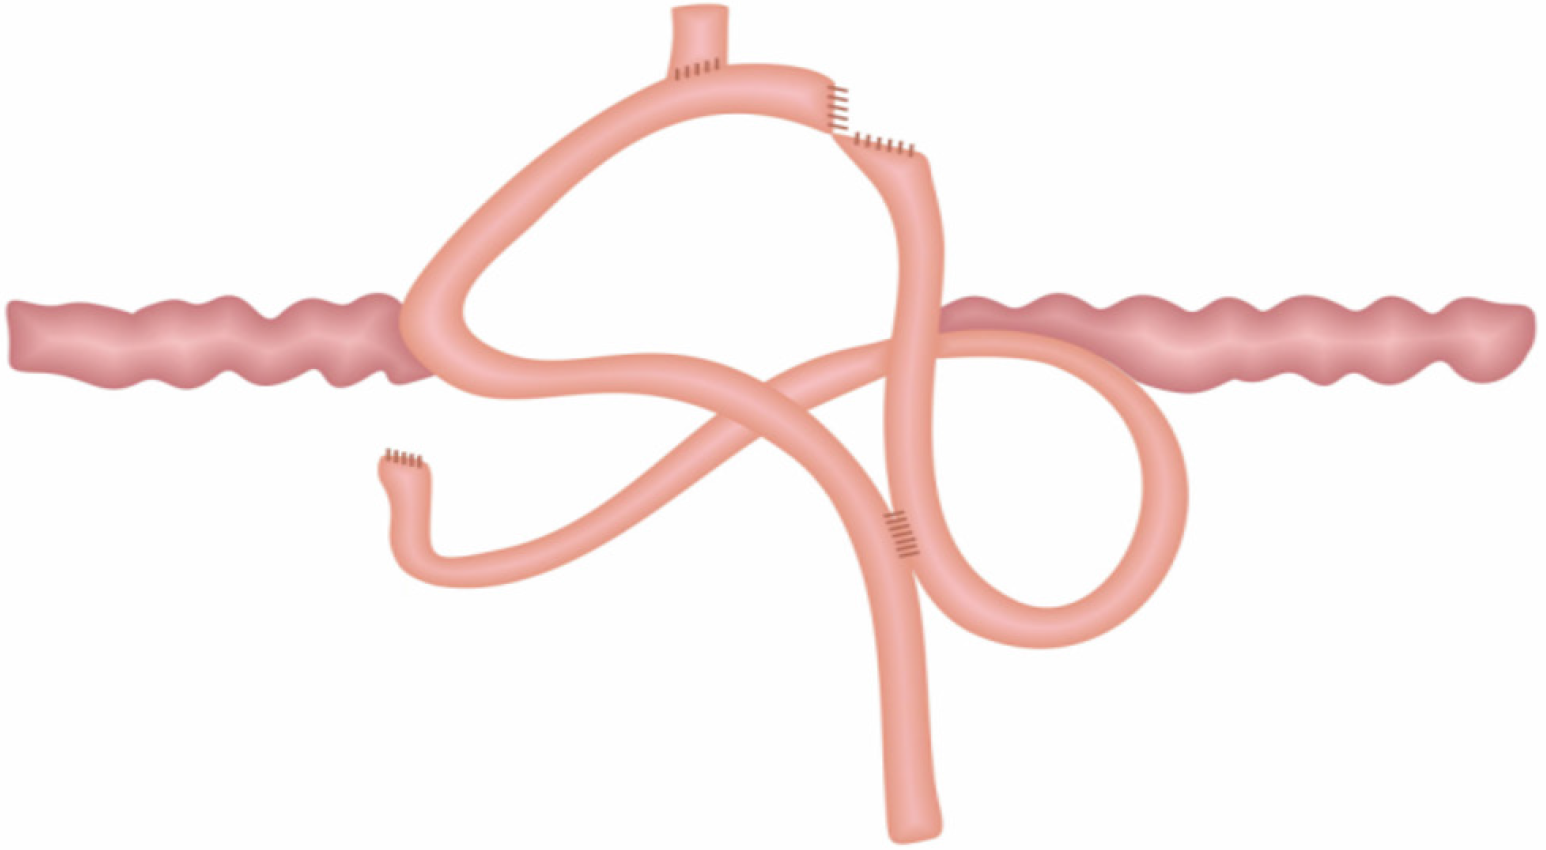

(1) A circular stapler buttress was embedded in the jejunum approximately 65-70 cm distal to the ligament of Treitz. Then the jejunum was fenestrated approximately 15 cm distal to the ligament of Treitz, where a circular stapler was inserted to perform the side - side anastomosis of the proximal jejunum (approximately 15 cm away distal to the ligament of Treitz) and the jejunum (approximately 65-70 cm distal to the ligament of Treitz); (2) The circular stapler buttress was inserted into the lower segment of the esophagus, and then the circular stapler was inserted from the jejunum “fenestration” to perform end - side anastomosis of the jejunum (approximately 25 cm away from the flexor ligament) and the lower esophagus; (3) The jejunum was closed with a linear stapler; and (4) All anastomoses were embedded intermittently with silk thread (Figure 1).